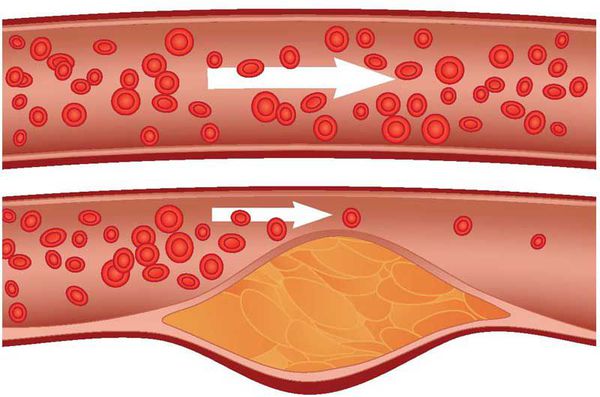

Атеросклероз – системное заболевание, при котором в первую очередь поражаются артерии. В стенке сосудов происходит отложение холестерина, вследствие чего образуются бляшки, препятствующие нормальному току крови.

Атеросклероз — системное заболевание, первоначально поражающее сосуды, но не все, а только артерии, в стенках которых накапливается холестерин и его эфиры, образующие характерные для этого заболевания бляшки. [1]

Холестерин и атеросклероз

«Генетическими поломками» вызвана так называемая семейная гиперхолестеринемия, при которой перемещающиеся в крови комплексы липидов, содержащие холестерин, плохо захватываются тканями (прежде всего, печенью). В результате концентрация в крови этих частиц и, соответственно, холестерина, возрастает, и избыточный холестерин, а также его эфиры оказываются в конечном счете в стенке артерий. Конечно, процесс этот гораздо сложнее и в действительности является многоэтапным, но конечный результат его — образование атеросклеротических бляшек в стенках сосудов.

Патогенез атеросклероза

Рост атеросклеротических бляшек — процесс, растянутый на долгие годы и десятилетия. Если бляшка в стенке сосуда достигает значительных размеров (около 70% просвета сосуда или более того), она может создавать существенные препятствия для кровотока и для кровоснабжения соответствующего органа — например, сердца или мозга. Бляшки, небольшие по размерам, тоже небезопасны — при разрыве таких бляшек (это возможно в случаях, когда истончается по разным причинам их «покрышка») в месте разрыва возникает образование тромба, который может полностью перекрыть просвет сосуда. [5] В этом случае из-за резкого ограничения кровотока возникает гибель значительного количества клеток органа, кровоснабжаемого данным сосудом — инфаркт (например, инфаркт миокарда или инфаркт мозга — инсульт, возникающий при атеросклерозе сосудов головного мозга).